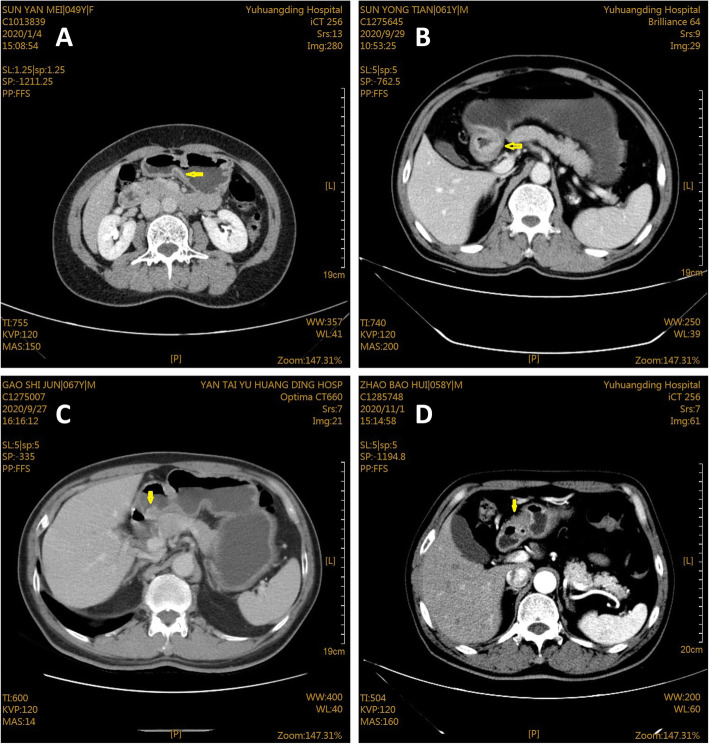

The imaging results of GC examined by MDCT

As shown in Fig. 4, patients at T1 stage showed thickening of gastric wall with enhancement of inner layer, as well as visible complete low density band in submucosa (Fig. 4A). While for T2 stage (Fig. 4B), there were thickening of gastric wall, smooth outer edge of gastric wall, and focus breakthrough of low-density zone. For patients with T3 stage, imaging displayed irregular outer serosa margin of thickened gastric wall, blurred space with adipose layer, and presence of nodules (Fig. 4C). Besides, for stage T4 in Fig. 4D, there were blurred serosa and mucosa surface of the gastric wall, unclear adipose layer space, and invasion in the adjacent organs.

Fig. 4.

MDCT image